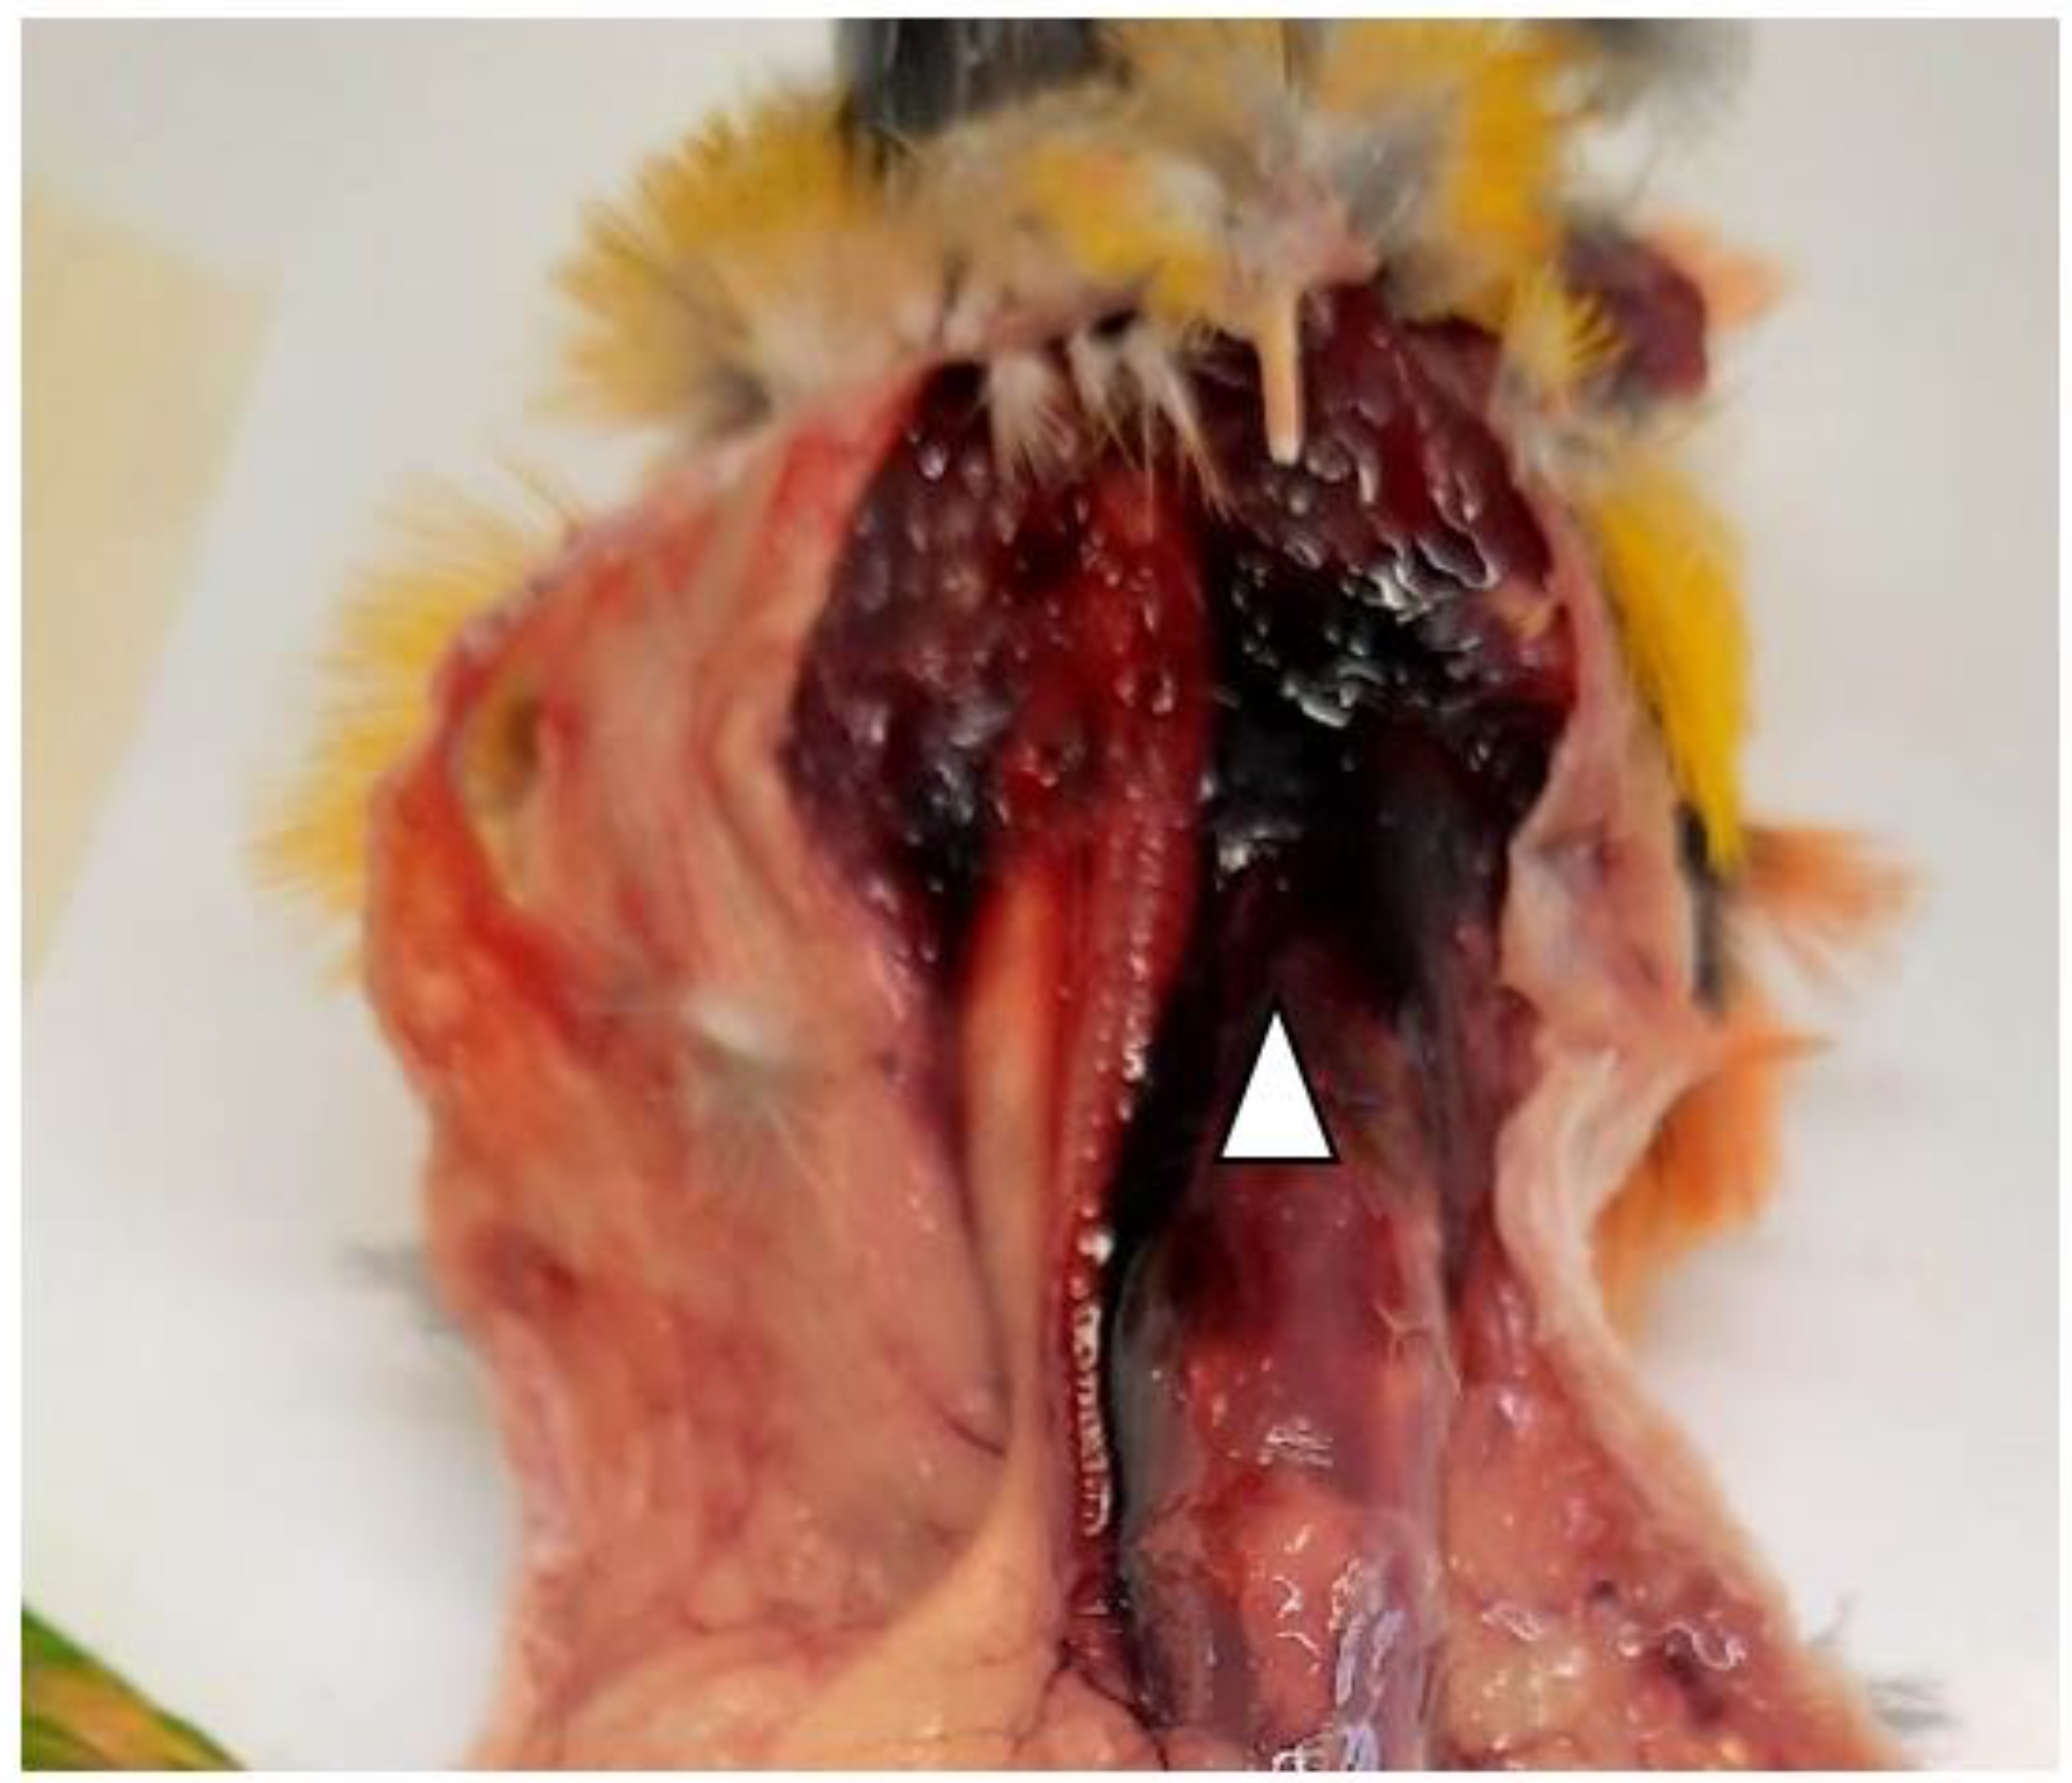

Each bird was lodged in contiguous cages within the same pet shop. Two birds died during this outbreak. The first one was an adult (three-years-old female) of Black-headed Caique Parrot (Pionites melanocephalus), whose carcass was sent to the laboratory of the Istituto Zooprofilattico Sperimentale (IZS) della Sardegna, section of Cagliari for post-mortem examination. The pet shop owner reported that the death of the bird was unexpected since the bird did not show evident clinical signs, except for the isolation of the animal from the other parrots that were in the cage. Ten days after the Caique, a rosy-faced lovebird (Agapornis roseicollis) died, and its carcass was sent to IZS della Sardegna for further analysis. The newly introduced parrot was kept alone in a separate cage, and it was quarantined for an undefined period. The medical history reported anorexia, lethargy, and dyspnea. The owner admitted that when the bird did not completely eat the food, the leftovers were distributed in other cages. Unfortunately, the necropsy of the Agapornis roseicollis was not possible due to autolysis of internal organs. On the other hand, the anatomo-pathological analysis was only performed on the Caique and showed a clear presence of regurgitation in the oral cavity, hyperemic and congestive neck region (Figure 1) associated with ectasia of blood vessels.

Figure 1.

Hyperemic and congestive neck region (white arrowhead) identified during the necropsy of the Caique.